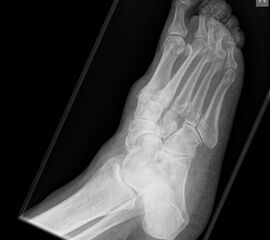

Die isolierte Arthrose der Bona Jäger Gelenkreihe (navikulocuneiforme Gelenk) ist selten und oft posttraumatisch. Meistens geht die navikulocuneiforme Arthrose mit einem schmerzhaften Pes planovalgus einher 2425. Letztlich werden die betroffenen Gelenkflächen angefrischt und mittels verschiedener Implantat-Möglichkeiten (s.o.) fusioniert. Bei gleichzeitiger Plattfußfehlstellung sollte diese ebenfalls adressiert werden 26 (Abb. 4). Ziel ist die Arthrodese in anatomischer Stellung der Gelenke.

Die Operation erfolgt meist über einen medialen Zugang. Nach Entknorpeln der  Gelenkflächen und Anfrischen des subchondralen Knochens kann die Arthrodese mit Schrauben oder Plattensystem erfolgen (Abb. 5). Bei Fehlstellungen muss diese vor der Osteosynthese korrigiert und das Talonavikulargelenk reponiert werden. Pseuarthrosen werden hier zwischen 8-25% angegeben 3223.